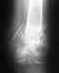

снимок 14.07.11

после которого разрешили не носить лангету и разрабатывать потихоньку руку

но лангету я продолжил одевать на ночь

• Кликните для загрузки файла 11. стержень 14.07.11.jpg